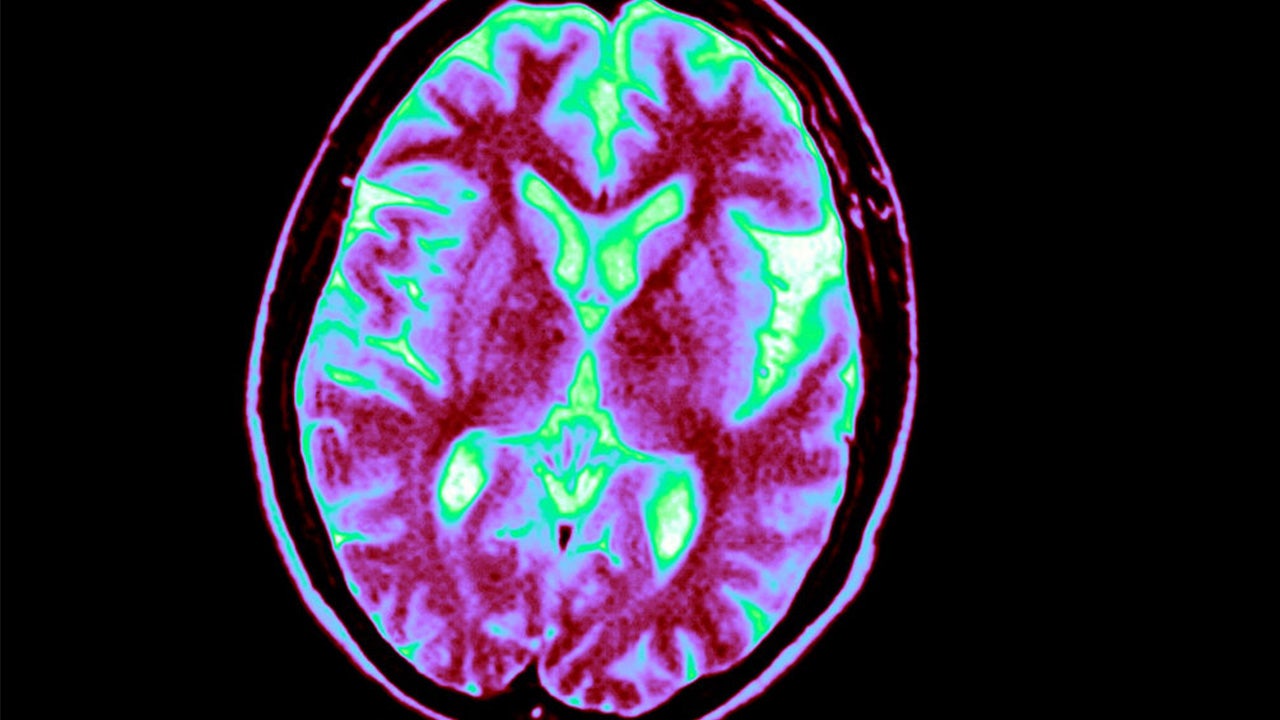

FILE - Voluminous Left Sylvian Fissures. Cortical Sulci And Posterior Horns Of The Lateral Ventricles Are Enlarged. Axial Cut Away View. (Photo By BSIP/UIG Via Getty Images)